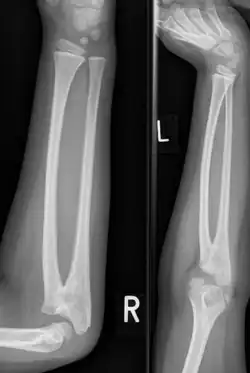

Plain radiograph showing fusion of the radius and ulna

Congenital radioulnar synostosis in a 7-year-old boy

Radioulnar synostosis is a rare condition where there is an abnormal connection (synostosis) between the radius and ulna bones of the forearm.[1] This can be present at birth (congenital), when it is a result of a failure of the bones to form separately, or following an injury (post-traumatic).[2]

Diagnosis at birthday is best done using ultrasound technology. In younger children and adults, diagnosis is done with x-ray machine at the radioulnar bones.